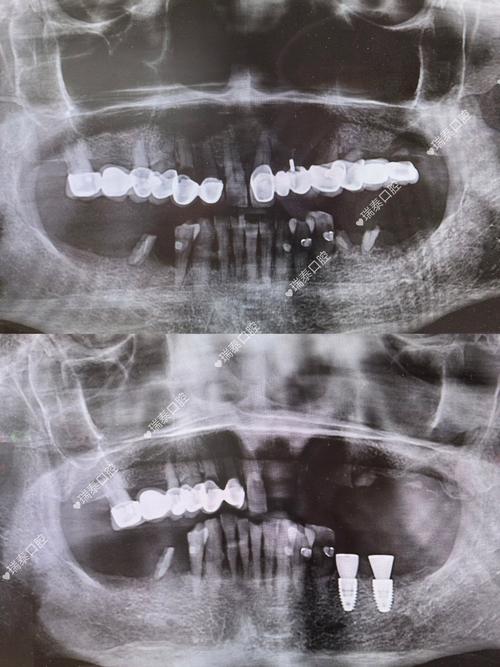

种植牙的成功,离不开精准的影像检查,现代口腔种植常用的影像技术包括根尖片、曲面断层片及锥形束CT(CBCT),其中CBCT因三维成像、高分辨率、辐射剂量可控等优势,已成为种植术前的“金标准”,拍片的核心作用体现在以下方面:

精确测量骨量,制定安全植入方案

CBCT可三维重建牙槽骨形态,清晰显示骨的高度、宽度、密度,以及骨内凹陷、缺损区域,医生通过软件分析,可精确计算种植体的直径、长度,选择合适的种植体型号,确保种植体植入后周围有至少1-2mm的骨壁包裹,提供初期稳定性,对于牙槽骨严重萎缩的患者,可通过CBCT判断是否需要植骨、骨增量手术的量及范围,避免盲目种植。

定位重要解剖结构,规避手术风险

CBCT能清晰显示下牙槽神经管、上颌窦底、颏孔、鼻腭管等解剖结构的位置及走行,下颌后牙区的种植体需距离下牙槽神经管至少2mm,上颌后牙区的种植体需距离上颌窦底至少1mm,CBCT可帮助医生精准标记安全植入范围,避免神经损伤和上颌窦穿孔,对于邻牙牙根倾斜、弯曲的情况,CBCT可明确牙根形态,确保种植体与牙根间保持足够距离(至少1.5mm)。

评估全身及口腔整体状况,排除种植禁忌症

拍片不仅是局部检查,还可结合患者全身情况(如是否有糖尿病、骨质疏松症等)及口腔整体健康(如是否有根尖炎症、囊肿、埋伏牙等)综合评估种植可行性,CBCT可发现牙槽骨内的囊肿或病变,需先治疗再种植;对于骨质疏松患者,可评估骨密度,调整种植体植入方案(如选择表面粗糙的种植体增强初期稳定性)。